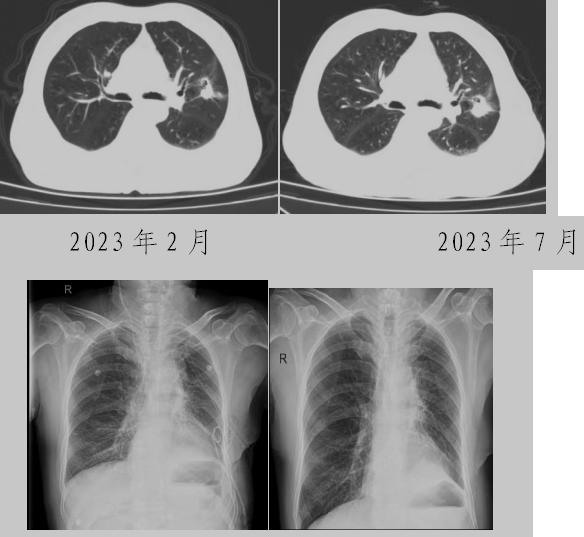

病例一:70多歲的患者王先生于2020年“急性心梗”入院時(shí)檢查發(fā)現(xiàn)了肺部結(jié)節(jié),王先生沒有在意,其間未規(guī)范復(fù)查胸部影像學(xué)檢查,于2023年2月份再次發(fā)作心絞痛時(shí),發(fā)現(xiàn)肺結(jié)節(jié)已發(fā)展成直徑約2.5cm實(shí)性腫塊,患者在家長期口服“替格瑞洛及腸溶阿司匹林”等抗凝藥物,生活可自理,于冠狀動(dòng)脈二次植入支架后三個(gè)月,收住市二院胸外科,經(jīng)心內(nèi)科、麻醉科等多學(xué)科會(huì)診后,由胸外科主任王松陽、副主任醫(yī)師薛飛及科室團(tuán)隊(duì)行“單孔胸腔鏡下左上肺癌根治術(shù)”,術(shù)后結(jié)合快速康復(fù)理念,三天后拔除胸管,一周出院。